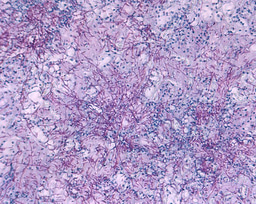

Does the in vitro finding of GM as a TLR4 ligand have any in vivo implications? To explore this, we investigated whether GM affords any protective effects against the DSS-induced colitis model in mice. First of all, we showed that daily intraperitoneal administration of GM does not trigger inflammation in healthy mice alone; nevertheless, it effectively mitigates colonic inflammation in wild-type mice with DSS-induced colitis, in terms of immune cell infiltration, proinflammatory marker expressions, and histological analysis. Importantly, the protective effects of GM were abolished in TLR4-/- mice, consistent with our in vitro results of GM as a TLR4 ligand. Overall, these in vivo findings underscore the therapeutic potential of natural gut microbiota–derived disaccharides in alleviating intestinal inflammation in the host.